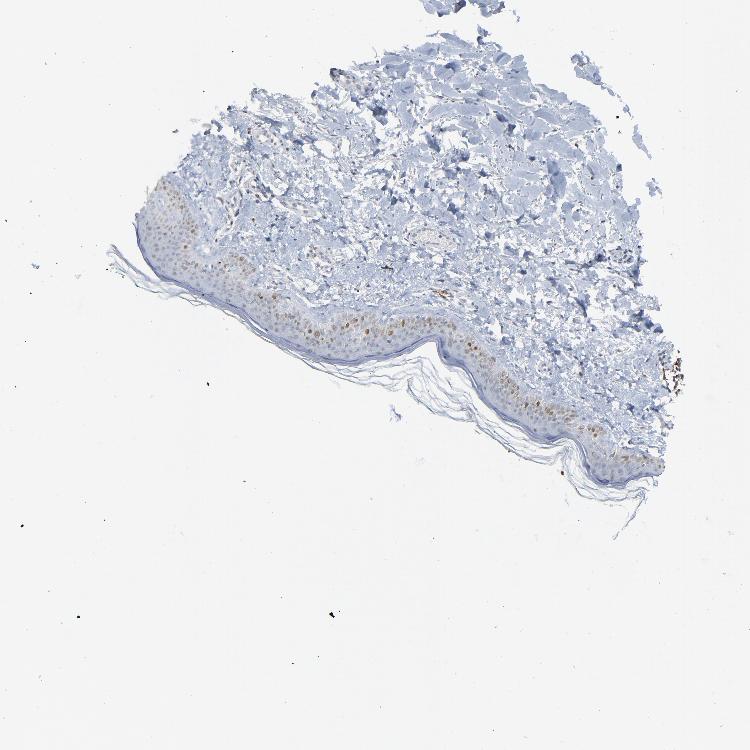

SKIN 1 - Antibody stainingi

Antibody staining in the annotated cell types in the current human tissue is reported as not detected, low, medium, or high, based on conventional immunohistochemistry profiling in selected tissues. This score is based on the combination of the staining intensity and fraction of stained cells.

Each image is clickable and will lead to virtual microscopy that enables deeper exploration of all samples and also displays staining intensity scores, fraction scores and subcellular localization as well as patient and tissue information for each sample.

Antibody HPA002317

Arrector pili muscle cells Not detected

Cells in basal layer Low

Cells in corneal layer Not detected

Cells in granular layer Not detected

Cells in spinous layer Low

Eccrine glands Medium

Endothelial cells Not detected

Extracellular matrix Not detected

Fibrohistiocytic cells Not detected

Langerhans cells Not detected

Lymphocytes Not detected

Melanocytes Not detected

Vascular mural cells Not detected